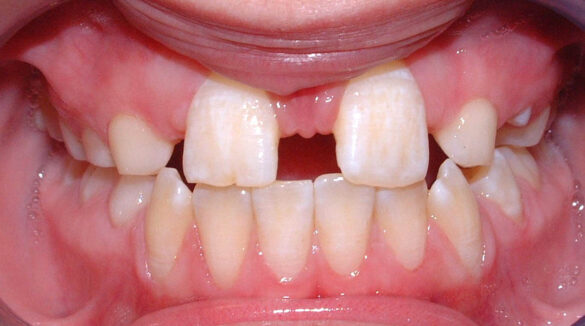

A doua etapă a tratamentului a fost amânată până în aprilie 2006, când pacienta a împlinit vârsta de 11 ani şi 5 luni. În acel moment, fetiţa prezenta erupţie şi dezvoltare radiculară adecvată, astfel că aparatele fixe aplicate acum n-ar fi purtate o perioadă îndelungată. Ocluzia inversă frontală şi angrenajul invers lateral fuseseră corectate; totuşi, exista o diastemă mare, în principal cauzată de lipsa incisivilor laterali superiori (fig.3). În acest moment, radiografia panoramică relevă anodonţia incisivilor laterali maxilari şi a premolarului secund drept mandibular, o anatomie redusă a rădăcinilor incisivilor centrali superiori, incluzia caninului superior stâng şi dezvoltarea întârziată a rădăcinii celui de-al doilea premolar inferior (fig. 4).